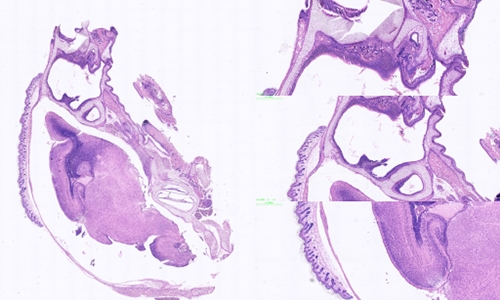

冰冻切片和石蜡切片是常见的组织学研究中的两种切片技术,它们在样本处理和切片制备过程中存在一些区别。

样本处理方面:冰冻切片主要适用于新鲜组织或不含脂肪的组织,如肌肉、肾脏和神经组织等。在进行冰冻切片前,组织样本通常被快速冷冻,并使用冰冻剂(如液氮)来保持样本的冷冻状态。而石蜡切片则适用于各种类型的组织,包括脂肪组织。在进行石蜡切片前,组织样本通常需要进行固定、脱水和浸泡等处理步骤,最后嵌入到石蜡块中进行切片。

切片制备方面:冰冻切片的制备相对较快速简便。在冰冻切片过程中,组织样本从冷冻状态转移到切片机上进行切割,通常需要使用冰冻切片机和低温切片刀来确保样本的冷冻状态。而石蜡切片的制备相对复杂。在石蜡切片过程中,需要将经过处理的组织样本嵌入到石蜡块中,然后使用石蜡切片机进行切割。由于石蜡具有一定的硬度,因此需要使用高速旋转的刀片来切割并得到薄片。

切片质量方面:冰冻切片相对于石蜡切片来说,切片质量可能稍差。由于冰冻切片的过程较快,切片的质量受到冷冻状态的影响,容易出现组织断裂、伪影和冰晶等问题。而石蜡切片在固定和浸泡处理后,组织样本得到更好地保护,切片质量相对较好。

切片的用途方面:冰冻切片主要用于快速初步观察和诊断,例如快速冰冻切片可以用于术中病理诊断。而石蜡切片则适用于各种组织学研究,包括光镜下观察、免疫组化染色和分子生物学研究等。

石蜡切片是两种常见的组织学切片技术,选择合适的切片技术取决于研究的目的、组织类型以及需要的切片质量。无论是冰冻切片还是石蜡切片,它们都为组织学研究提供了重要的工具和手段。